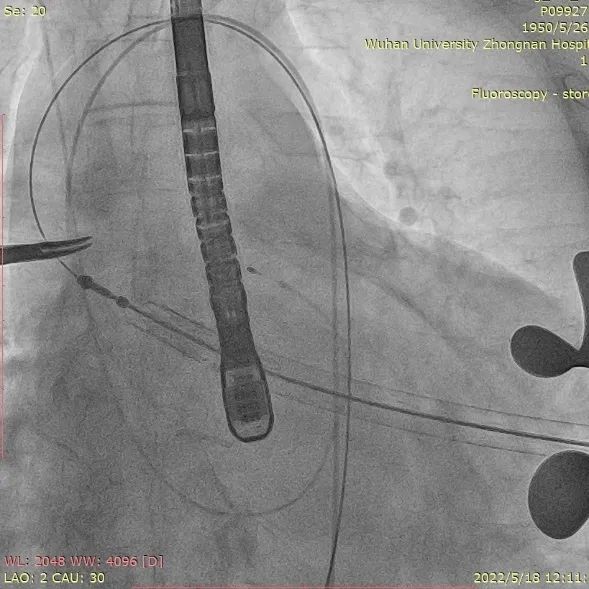

4. 患者术中造影角度LAO:2°,CAU:30°;

术中造影角度:LAO:2°,CAU:30°

手术过程:

取平卧位,行右侧股动脉穿刺,置入6F鞘管,注入7000U肝素,分别送EBU3.75、EBU4.0、JL4指引导管均未能到达左冠口,EBU4.0塑型后成功达到左冠口,送VT导丝至前降支远端,送BMW导丝至回旋支远端,送2.0*20mm双导丝球囊于前降支近段狭窄处充分预扩张;送波科3.0*24mmDES一枚至前降支中段病变处,精准定位后释放,分别送3.5*16mm乳突球囊、3.0*15mmNC球囊至支架内修饰扩张。复查造影示支架膨胀良好,撤除鞘管,常规加压包扎,注意有无出血及高迷走反射。

全麻后,右颈静脉置入5F临时起搏电极至右室流出道备用。DSA指引下左胸第6肋间前外侧切5cm进胸,切开心包并悬吊,TEE引导下心尖处2-0prolene线带毛毡片缝双层荷包,全身肝素化,右股动脉穿刺置入5F猪尾至无冠脉窦底并行主动脉根部造影。心尖荷包穿刺置入泥鳅导丝及5F单弯导管至降主动脉,交换头部塑性后的Lunderquist加硬导丝,24F鞘管扩张,将装载29#J-Valve瓣膜的输送装置经过加硬导丝送入主动脉根部。打开定位件,回拉落入三个瓣窦,依次释放瓣膜,瓣膜释放后造影及TEE评估瓣膜位置及功能良好, 锁丝脱钩后撤出输送器。单弯管保护下撤出加硬导丝,再次造影确认瓣膜功能良好、升主动脉及入路血管无损伤,心尖处荷包打结。止血后留置左侧胸管一根并常规关胸。过程顺利,患者术后转ICU监护。

植入器进入升主动脉

定位件入窦后瓣膜落座